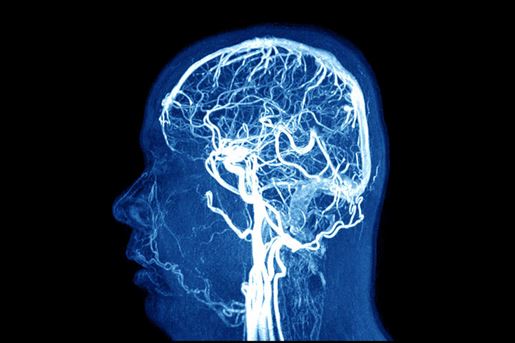

Indications for the Performance of Intracranial Endovascular Neurointerventional Procedures

- This Statement offers an update on the rapidly evolving field of endovascular neurointerventions, which use minimally invasive techniques to treat a wide spectrum of diseases.